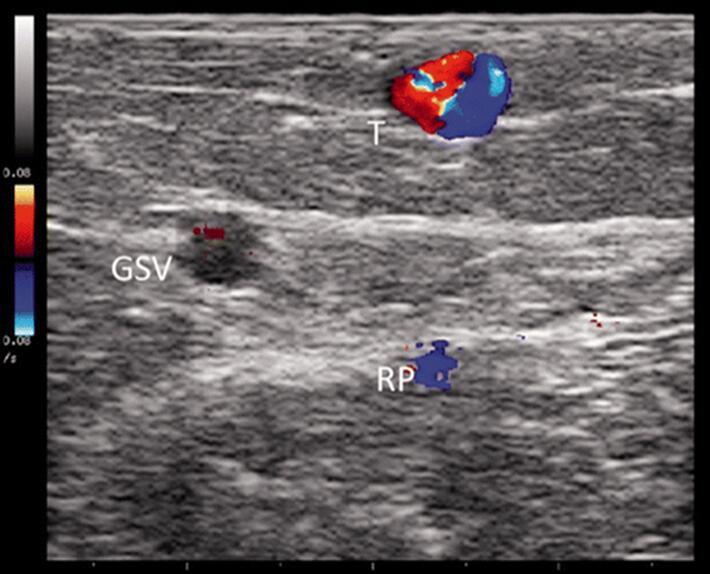

图19。功能不全的大隐静脉属支扫描。彩色模式检测到大隐静脉属支血流紊乱的表现(韩国国旗征)。功能不全的属支位于筋膜之上(属于N3系统(室)提示明显比大隐静脉直径要粗(GSV)(N2系统),位于同一个属支出口下方。一个彩色标志点提示存在(RP)点穿通支。